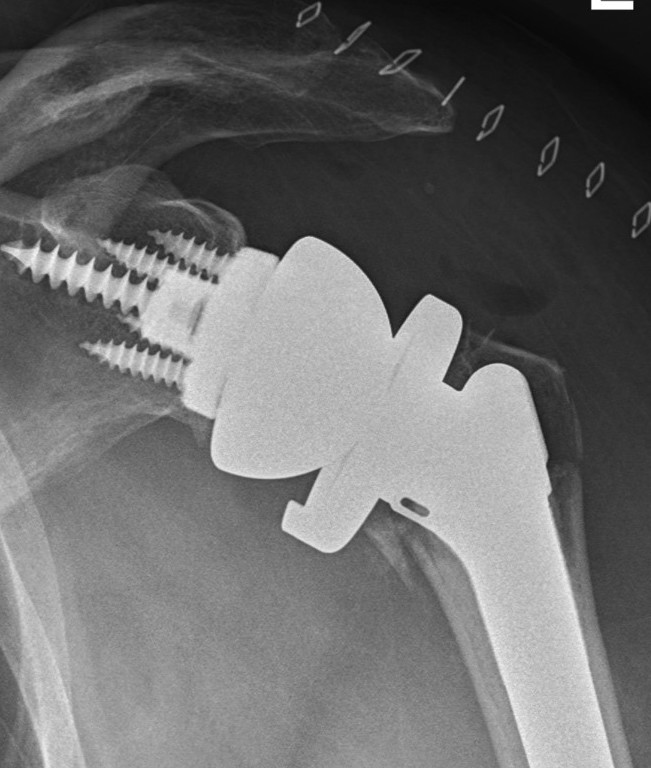

Reverse total shoulder arthroplasty

- elderly patients

- better outcomes than hemiarthroplasty

Indications

Unreconstructable fracture in elderly > 65

- comminuted, 3 or 4 part

- head spltting fracture

- off ended / 100% displaced